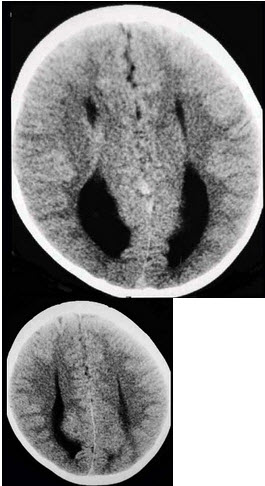

女,一岁,发育低于同龄幼儿,CT检查如图,最可能的诊断为( )

A:透明隔囊肿

B:前脑无裂

C:无脑回

D:胼胝体发育不良

E:无脑回伴胼胝体发育不良